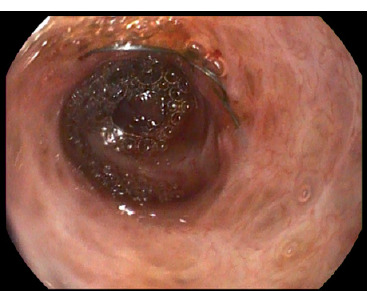

Figure 4

A plastic biliary 10 fr 90 mm Amsterdam- type stent passed through the stenosis after its ablation to prevent further narrowing